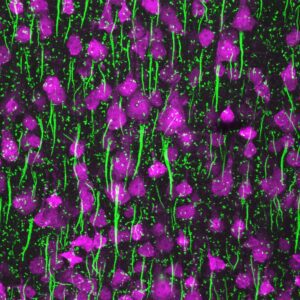

In het ‘signaalverwerkings-lab’ worden inmiddels hooggespecialiseerde metingen op nanometerniveau gedaan met behulp van glaspipetten en fluorescerende stoffen. Dat is bijzonder, want er zijn maar een paar laboratoria in de wereld die elektrische spanning met behulp van kleur kunnen laten zien.

Kole probeert te meten wat dat betekent voor de manier waarop de elektrische geleiding plaatsvindt en de wijze waarop de actiepotentialen zich precies verplaatsen. Een heel ingewikkelde klus: ‘Die myelinelagen en zenuwcelmembranen zitten soms nanometers dicht naast elkaar, en bedenk dan dat één nanometer honderdduizend-maal kleiner is dan de diameter van een haar…’ Voor dat meetwerk kan Kole gebruikmaken van een nieuwe techniek. In de regel wordt elektrische spanning gemeten met versterkers, maar in Kole’s lab is een techniek ontwikkeld waarbij een fluorescerende stof de mate van spanning laat zien: ‘Een soort spanningszoeker waarbij de mate van lichtintensiteit aangeeft wat het potentiaalverschil is over een celmembraan.’ Dat beeld ziet er anders uit dan hij had verwacht: ‘Ik dacht dat er een golf zou zijn die op een constante manier doorloopt, maar er blijkt sprake van verspringingen in ruimte en tijd; iets wat we nooit eerder hebben gezien. Dat patroon vertelt ons ook iets over de myeline: hoe goed die isoleert, of dat anders in zijn werk gaat dan we nu denken, en of die überhaupt wel isoleert.’